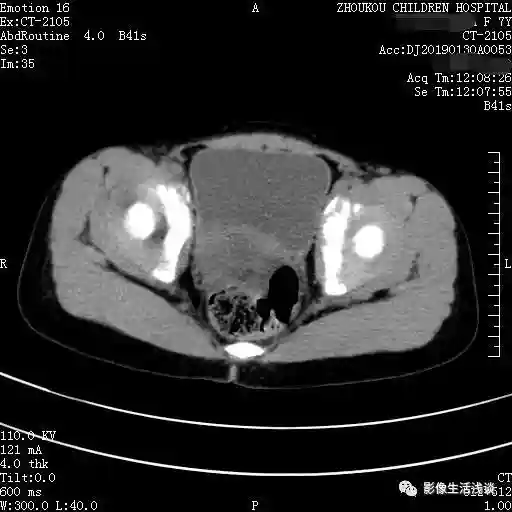

第二个病例女性63岁,体检CT中发现盆腔内左附件区囊性占位:

通过以上病例我们可以发现卵巢畸胎瘤CT表现,大部分情况下是呈多个囊性的病变,囊内套囊。每个囊的信号或者密度是不相同的,各个囊内的内容物也是不相同的。影像学常见的主要是脂肪、液体及骨骼等内容物,有一定的特征性的密度信号。在此情况下就提示是畸胎瘤,部分囊可以见到有头节形成的结节或肿块。如果囊壁的结节比较大呈肿块型,边缘不规则,囊外有侵犯有可能是恶性的。增强扫描囊壁与结节之间可有轻度或中度的强化,根据相应的CT的表现,同时也要结合女性相应的肿瘤标志物、临床表现,来给予综合的判断以及后续的处理,做到早发现早处理,降低恶性畸胎瘤的发病率。